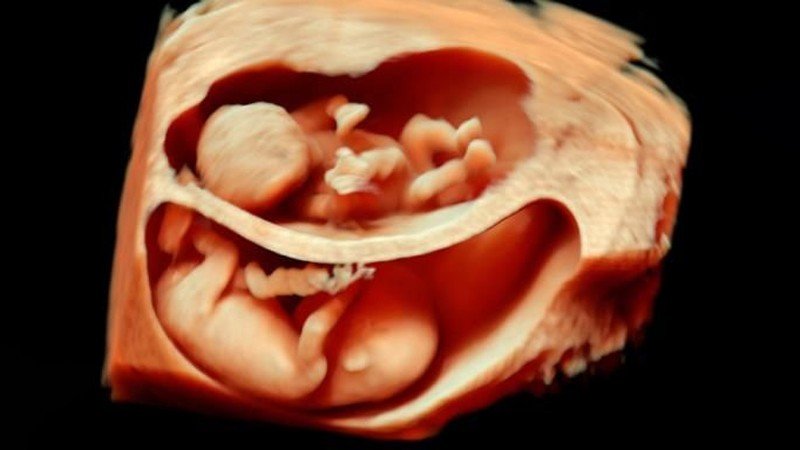

Ama giderek popülerleşen bir teknoloji sayesinde ebeveynler artık yavrularını çok daha net görebiliyorlar: 3D ve hatta 4D ultrason! Monako'daki Princes Grace Hastanesi'nde görev yapan Dr. Bernard Benoit, uzun yıllardır 3 boyutlu (ve hatta 4 boyutlu) ultrason görüntüleme teknikleri üzerinde çalışıyor ve çok başarılı sonuçlara da imza atmış vaziyette. Aşağıda, bunun bir örneğini görüyorsunuz.

Bu görüntüleme tekniği sayesinde, artık renkli ve çok daha net sonuçlara ulaşabiliyoruz. Bu görseller, bunun en net ispatlarından biri. Ana karnındaki ikizleri çok detaylı bir şekilde görüntülemek artık mümkün. Hem de o, uzaktan odaklanılmış bir kare. Aşağıdakiler, ne demek istediğimizi daha net anlatacaktır:

3D ultrasonlarda, birden fazla açıdan 2 boyutlu görüntüler çekiliyor ve sonrasında bilgisayar yardımıyla 3 boyutlu bir görsele dönüştürülüyor. Bu sayede bebeğinizin sadece bir kesidini değil, 3 boyutlu bir görüntüsünü elde etmeniz mümkün oluyor.

4D ultrasonlarda ise, 3D olan görüntüler zamana yayılmış bir şekilde kaydediliyor. Bu sayede bebeğin hareketlerini tıpkı bir video izler gibi görmeniz mümkün oluyor. Bu sayede bebeğin gözlerini açıp kapaması, gülümsemesi veya parmağını emmesi gibi olayları çok net bir şekilde görüntüleyebiliyorsunuz.